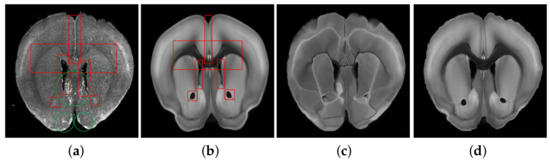

4.3.1. Rough Registration

Before fine registration, preliminary rough registration of brain slices and standard brain atlas can effectively reduce the difficulty of registration and improve the effect of fine registration. Therefore, choosing a suitable rough registration method is vital. In this study, affine transform, traditional B-splines [31], and Demons [32] were selected for testing, and the experimental results are shown in Figure 6. The performance comparison results using RT, NCC, and NMI measurement strategies are shown in Table 1. Obviously, affine transformation was the most suitable rough registration method because of its faster speed and better effect.

Figure 6. Examples across different transformation methods on the Atlas dataset. Top: Brain Slice image, ATA with different deformations. Bottom: Brain Slice image, ADA with different deformations.

Table 1. Comparison of the results of different methods of rough registration.

MethodCPU RT secNCCNMI

Original image pairs-0.5867571.068795

B-splines4130.7196631.085182

Demons2370.7333101.089640

Affine2190.8044991.097789